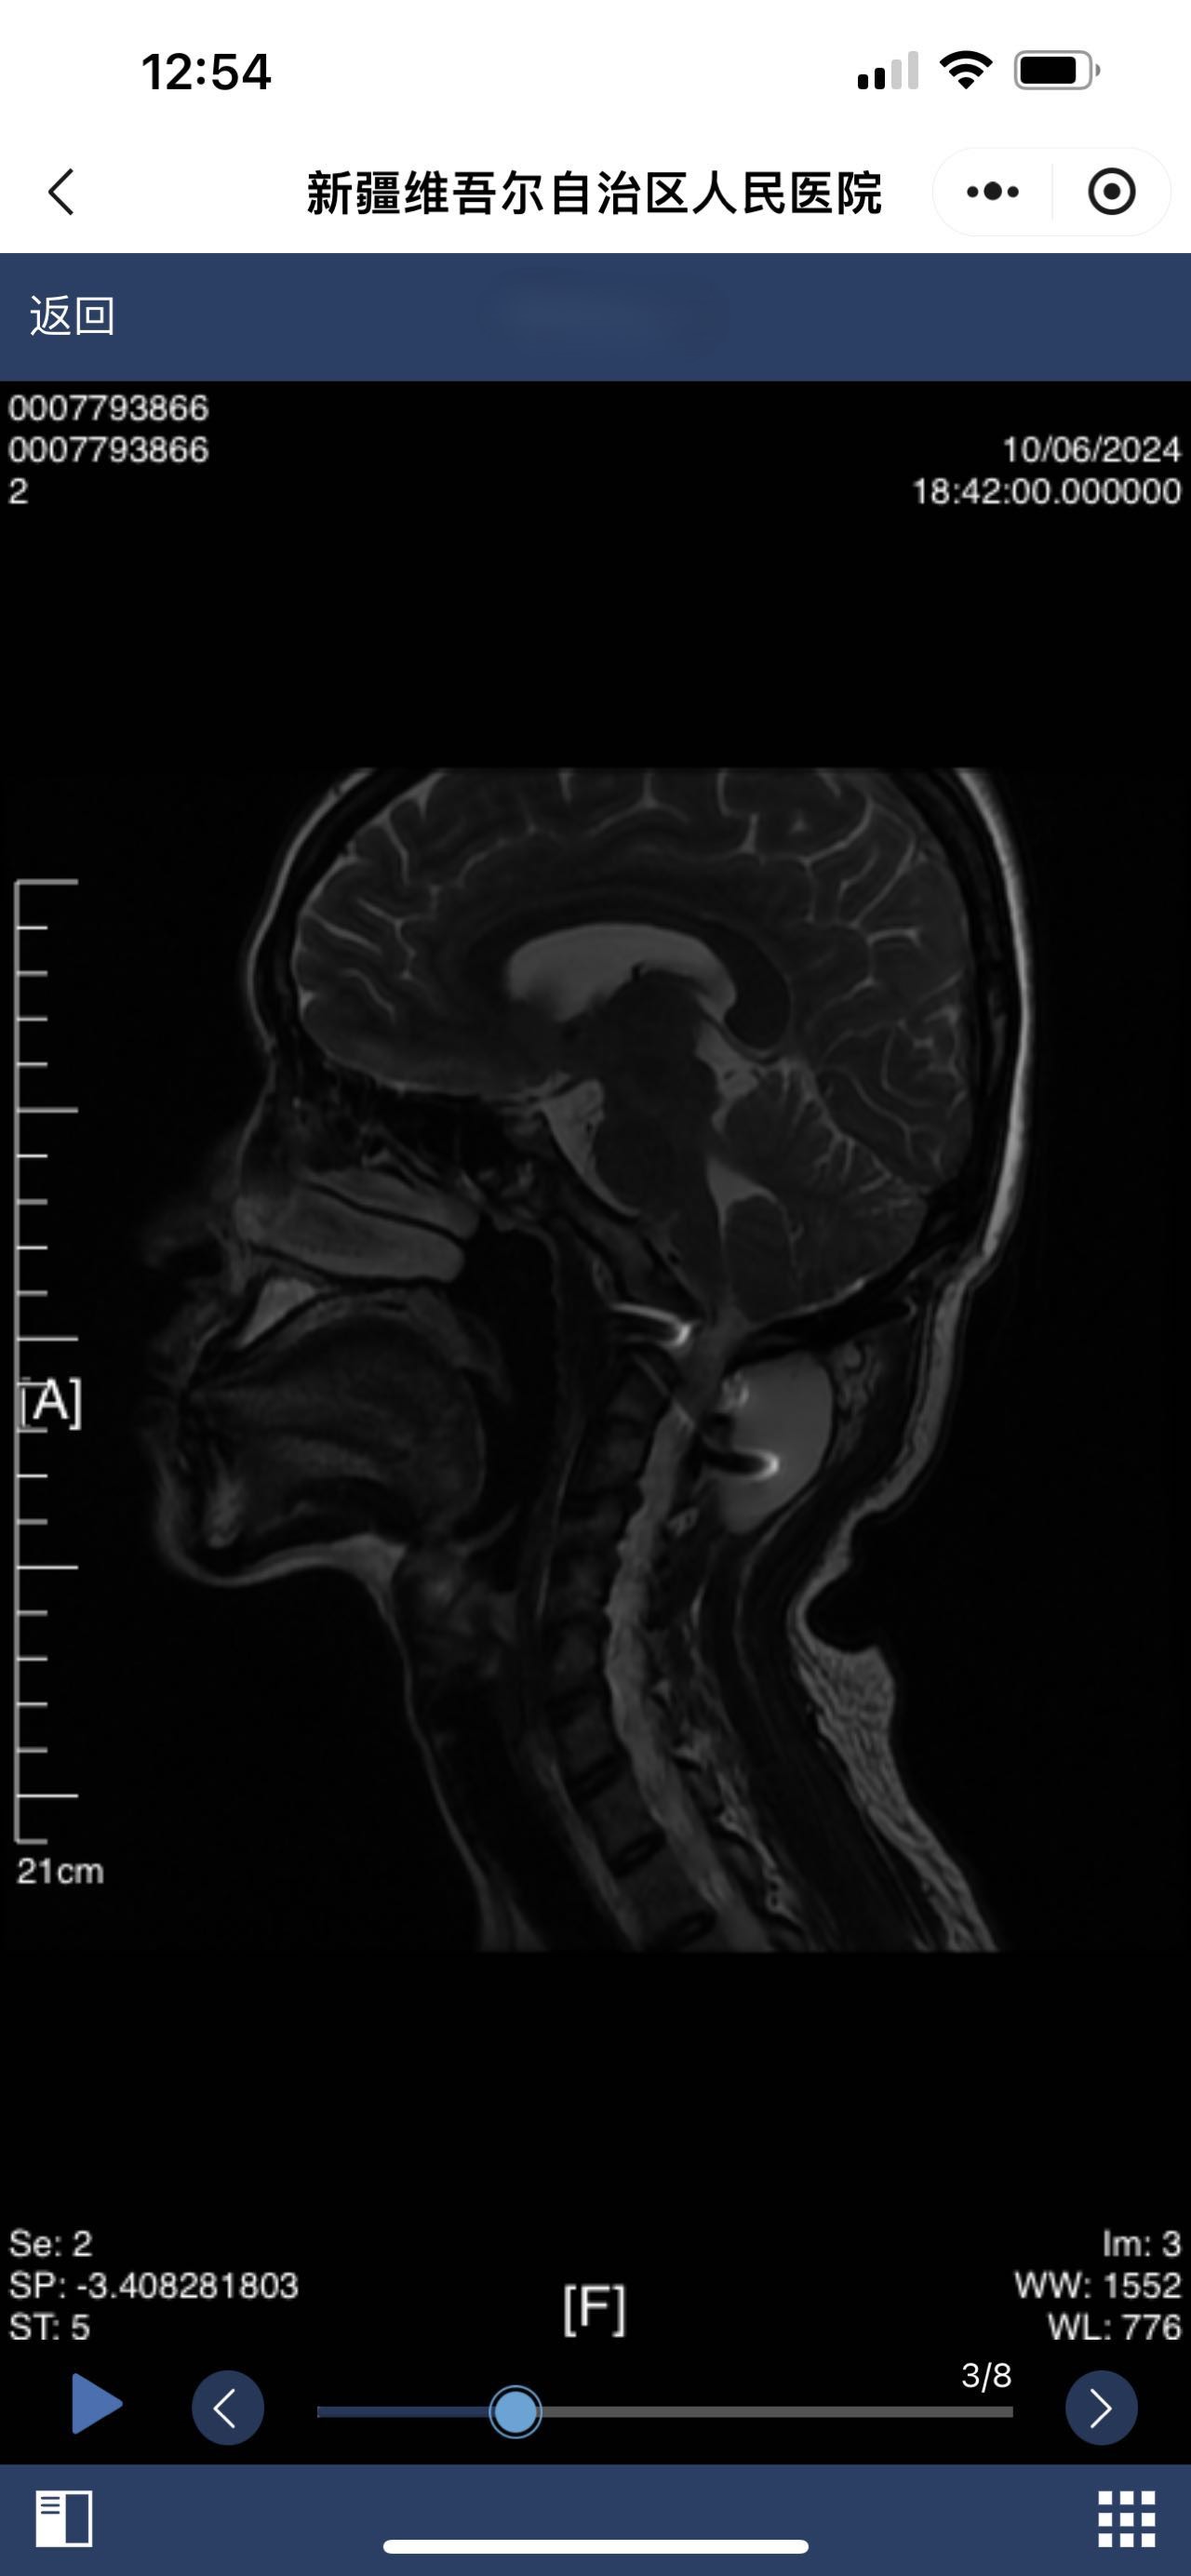

• 诊断:颅底凹陷

• 影像:

• 术后影像:

• 2024.10.06,积液范围略小。